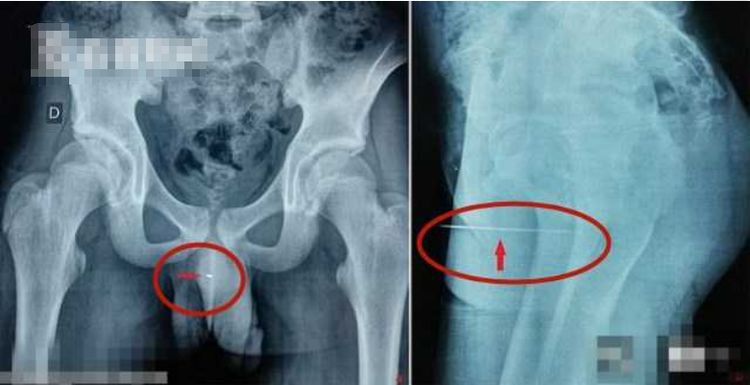

就在前段时间突尼斯某家医院又迎来了一位奇葩事情,十四岁小男孩有三天没有正常排尿了,下面很痛,医生就先让病人拍个片检查一下,当医生看到X光片的时候,医生都被眼前的一幕吓傻了,X光上面显示男孩的尿道里面有一根长达九厘米的缝衣针,据该男孩说当时只是为了好奇和得到快感才做出这样的事情。

在医生的帮助下,在小男孩的尿道5厘米处找到了那根9厘米的缝衣针的位置,然后对小男孩用了全身麻醉用镊子把针给取了出来,这次的手术非常的顺利,男孩在第二天就能出院了,然而医院方面却觉得这个小男孩可能有特殊性癖好才做出这样的事情。